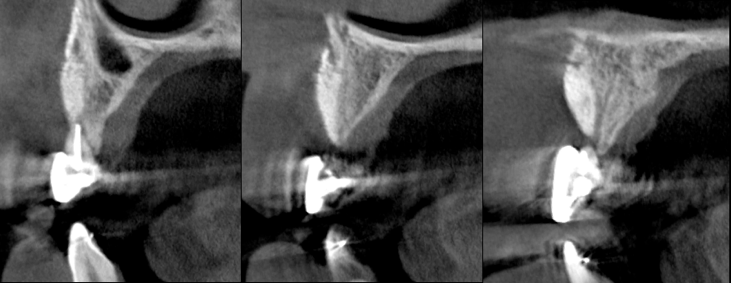

The patient had a congenitally missing upper right lateral incisor. Orthodontic treatment was performed to create the necessary space for a dental implant. Unfortunately, the implant failed, and so did several subsequent attempts to bone graft. These failures resulted in a visible smile deformity, that got worse after each failed procedure.

After the 3rd bone graft failed, the patient sought second opinions. She was a college sophomore at the time. Using a combination of interdisciplinary therapies, including S.M.A.R.T. minimally invasive bone grafting, Dr. Ernesto Lee was able to tridimensionally reconstruct this severe defect and place implants to restore the patient’s smile. The S.M.A.R.T. bone graft was also extended to treat adjacent teeth with thin/dehisced bone.

A long-term CAD/CAM fabricated temporary restoration is in place while she finishes medical school at an out-of-state university. The treatment of this case was published in detail in a special issue of the Compendium of Continuing Education in Dentistry, one of the largest circulation journals in our profession.